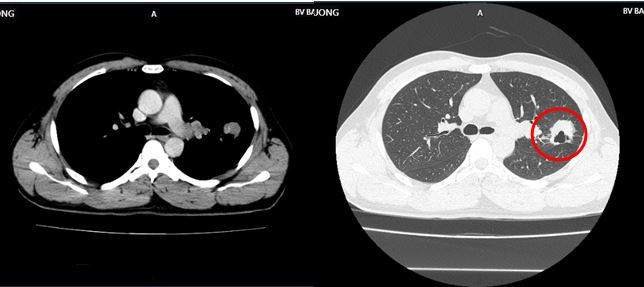

Bệnh nhân là anh H.V.H (43 tuổi) có tiền sử khỏe mạnh. Một tháng trước khi vào viện, anh H. ho khan và đau tức ngực trái. Người đàn ông này đi khám, chụp CT ngực phát hiện khối u thùy trên phổi trái kích thước 30x32mm, vài nốt mờ rải rác màng phổi 2 bên. Sau đó, anh nhập viện để điều trị.

H́nh ảnh khối u thùy trên phổi trái, kích thước 30x32mm (ṿng tṛn màu đỏ), vài nốt mờ rải rác màng phổi 2 bên của bệnh nhân. Ảnh: BVCC

Qua các xét nghiệm, chụp chiếu, bác sĩ chẩn đoán bệnh nhân mắc ung thư phổi trái, dạng biểu mô tuyến di căn năo. Bệnh nhân được chỉ định dùng thuốc điều trị đích thế hệ thứ 2: Afatinib 40mg/ngày.

H́nh ảnh CT ngực trước điều trị cho thấy u thùy trên phổi trái kích thước 30x32mm, vài nốt mờ rải rác màng phổi 2 bên. H́nh ảnh CT ngực sau 9 tháng thể hiện khối u phổi phải tiếp tục giảm kích thước 16x19mm, không c̣n hạch rốn phổi. Hạch trung thất không c̣n, tổn thương di căn năo đơn ổ biến mất, chất chỉ điểm khối u CEA, Cyfra 21-1 giảm về giới hạn b́nh thường.